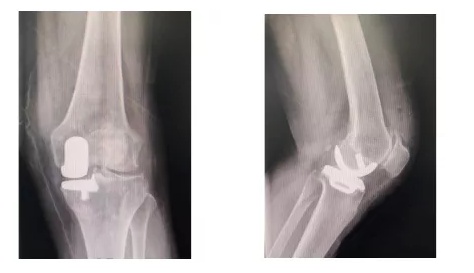

④ 单髁置换术:对于只是膝关节内侧髁磨损,外侧髁依然完好的患者,单髁置换手术将是更好的选择。这种人工关节保留了外侧髁、髌骨、交叉韧带等结构,与传统的全膝关节置换术相比,提供更多的生理功能、更大的活动范围、以及更快的术后恢复。